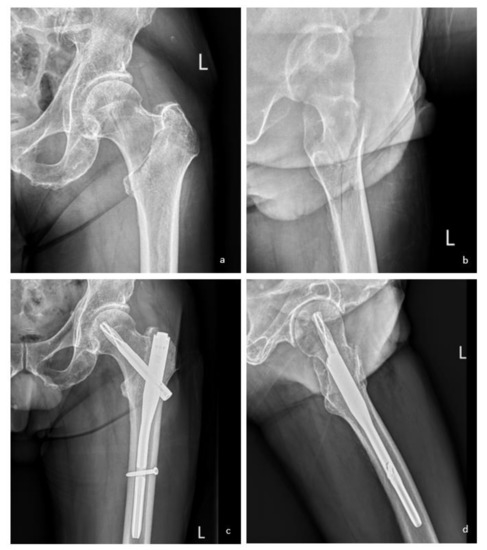

To demonstrate how the IT-AP tool would fit in clinical practice, we present a case of a 75-year-old male who presented with left hip pain and was subsequently diagnosed with an intertrochanteric fracture. To predict the likelihood of having good ambulatory status one year after the operation, the attending physician filled in all required predictor information into the IT-AP tool as shown in Figure 4 (Appendix C: Figure A4, Table A3). Then, the IT-AP tool under the preoperative model option estimated the LHR of having good ambulatory status after receiving operation at 4.7 (Appendix C: Figure A5a), which means that it was more likely than not that the patient would be able to ambulate at one year. In this case, the patient was scheduled for closed reduction and internal fixation with an intramedullary device (Appendix C: Figure A4a,b). After an initial adjustment, the orthopaedic surgeon wanted to know if the “current” adjustment was adequate. Surgical-related parameters were entered into the IT-AP tool under the intraoperative model option to estimate the LHR of ambulation considering fixation characteristics. The LHR was estimated at 3.70, representing a suboptimal surgical treatment (Appendix C: Figure A5b). The surgeon was then informed by the IT-AP tool that the “current” fixation and reduction characteristics were still inadequate and that further adjustment was still required (Appendix C: Figure A4c,d). Finally, after the surgeon performed additional surgical adjustments, the IT-AP tool revealed a LHR of 10.59, which was substantially higher than the predicted LHR from the preoperative model. Therefore, the surgeon decided to proceed with the skin closure and finish the operation (Appendix C: Figure A5c).

Figure A4.

To demonstrate the use of the IT-AP tool, an example of 75-year-old male patient presented with left hip pain after a simple fall diagnosed as intertrochanteric fracture information was applied to the application. After the required data was inputted (pre-injury NMS = 9, CCI = 4, BMI = 22.49 kg/m2) in the IT-AP tool application under the preoperative model option, the application calculated the likelihood ratio of good ambulatory status after receiving operation (LHR+ = 4.7) and have been informed to the patient. The patient was then transferred to the secondary hospital under specialists’ care and scheduled for closed reduction and internal fixation with an intramedullary device. The fracture was classified as AO/OTA 31A1 with a lateral wall thickness of 33.86 mm (a,b). Right after fracture reduction with near anatomical reduction was conducted (NSA = 129, neutral reduction in both dimensions) and internally fixed (CalTAD = 29.86, Parker’s ratio = 42%) (c,d), the IT-AP tool revealed a likelihood ratio of 10.59 to which surgeon decided to proceed with the skin closure and finish the operation.